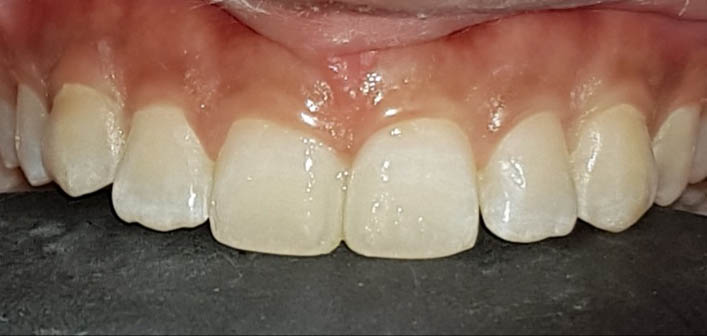

समोरचे दात जर किडलेले असतील तर त्यामध्ये दातांच्या रंगाचे फिलिंग (कंपोझिट) करता येते. खूपच किडलेल्या दातांना रूट कॅनाल ट्रीटमेंट करून, अगदी हुबेहूब नैसर्गिक दिसणारे सिरामिक किंवा झिरर्कॉनियम चे दातही बसविता येतात .

याशिवाय आजकालची प्रमुख समस्या म्हणजे पुढे आलेले दात किंवा दात वाकडेतिकडे असणे, दातांमध्ये फटी असणे की ज्यामुळे तुमचा चेहरा, तुमचं हसणं विद्रूप तर दिसतंच पण त्यामुळे खाताना, गिळताना, बोलतानाही त्रास होतो तो वेगळाच ... यावर दंततव्यगोपचार (ऑर्थोडोंटिक) हे प्रभावी माध्यम (उपचार) आहे. दाताना क्लिप्स लावून असे वाकडे तिकडे दात सरळ रेषेत येतात, पुढे आलेले दात मागे नेता येतात, दातातील फटीही बंद करता येतात. याशिवाय, जास्त वाढलेला जबड्यांची दुरुस्तीही योग्य तऱ्हेने करता येते. वाढीचे वय संपून गेल्यानंतरही, प्रौढांनाही कमी किंवा जास्त वाढलेल्या जबड्यावर शस्त्रक्रिया करून सुंदर चेहरा मिळविता येतो. उपचार चालू असताना अवघडल्यासारखे (awkward) वाटू नये म्हणून विशेषतः प्रौढांना, दातांच्या रंगाच्या, कमीत कमी दिसणाऱ्या क्लिप्स ही उपलब्ध आहेत. याच सोबत अलायनर्स(aligners)म्हणजे अजिबात न दिसणाऱ्या क्लिप्स सुद्धा उपलब्ध आहेत.